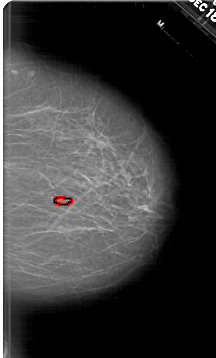

A_1633_1.RIGHT_CC

RIGHT_CC LINES 6436 PIXELS_PER_LINE 3886 BITS_PER_PIXEL 12 RESOLUTION 43.5 OVERLAY

FILE: A_1633_1.RIGHT_CC.OVERLAY

TOTAL_ABNORMALITIES 1

ABNORMALITY 1

LESION_TYPE CALCIFICATION TYPE PLEOMORPHIC DISTRIBUTION CLUSTERED

ASSESSMENT 4

SUBTLETY 3

PATHOLOGY BENIGN

TOTAL_OUTLINES 1

BOUNDARY